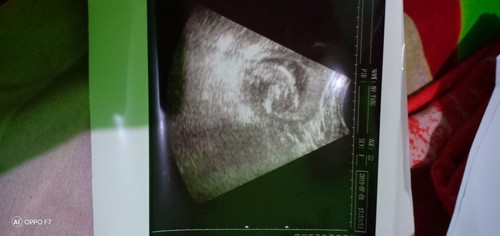

Foto USG tanggal 1 bulan Juli 2019

USG tanggal 1 bulan Juli 2019 Sudah terlihat bentuk tulang anak ku Anak ku meringkuk di dalam rahim ku Sehat terus yaa anak Bunda Jadi anak pinter yaa sayang Bunda rela muntah setiap hari demi kamu Bunda sayang kamu, nak ?